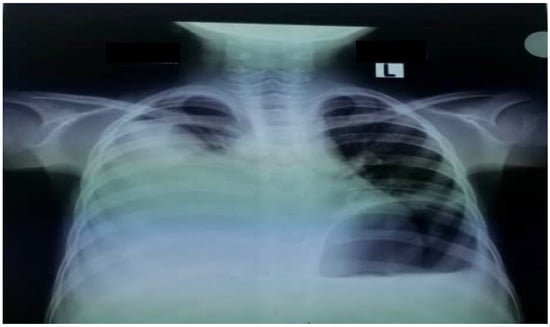

The patient was admitted to the pediatric intensive care unit (PICU) because of tachypnea, hypoxemia, and subcostal retraction. An urgent chest X-ray revealed a right pleural effusion (Figure 1).

Figure 1. Chest X-ray of the patient showing right pleural effusion.